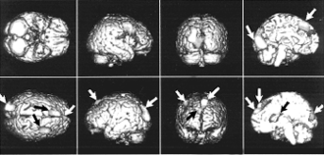

| Интересные результаты даёт такой эксперимент. Испытуемому рассказывают одновременно две разные истории: в левое ухо одну, в правое — другую. На верхнем фото изображены разные проекции мозга — стрелками отмечены активизированные зоны, когда внимание сосредоточено на истории, рассказываемой в левое ухо. Внимание испытуемого „переключилось“ на „историю в правом ухе“ (нижнее фото). Можно заметить, что для фиксации внимания на „историю в правом ухе“ требуется гораздо меньшая активность мозга. Это связано с праворукостью большинства людей — обычно они берут телефонную трубку правой рукой и прикладывают её к правому уху. |

Кроме непроизвольного внимания есть ещё и селективное. Это так называемое „внимание на приёме“, когда все вокруг говорят разом, а вы следите только за собеседником, не обращая внимания на неинтересную вам болтовню соседа справа. Во время эксперимента испытуемому рассказывают истории: в одно ухо — одну, в другое — другую. Мы следим за реакцией на историю то в правом ухе, то в левом и видим на экране, как радикально меняется активизация областей мозга. При этом активизация нервных клеток на историю в правом ухе значительно меньше — потому, что большинство людей берут телефонную трубку в правую руку и прикладывают её к правому уху. Им следить за историей в правом ухе проще, нужно меньше напрягаться, мозг возбуждается меньше.